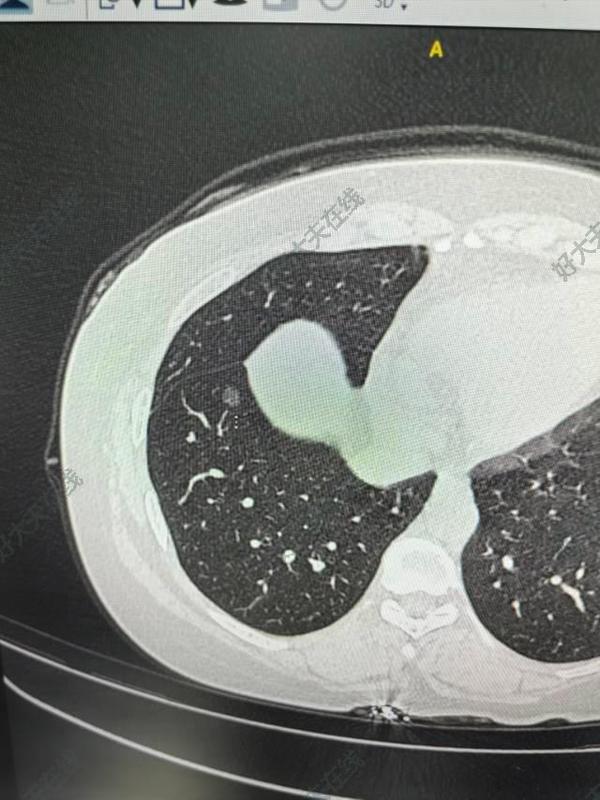

治療前患者查體發(fā)現(xiàn)右肺下葉約6mm磨玻璃結(jié)節(jié),考慮微浸潤(rùn)腺癌可能,患者中年女性,身高145,體重135斤。治療中與麻醉科王勝剛主任討論后決定行高流量吸氧自主呼吸下胸腔鏡右肺下葉部分切除術(shù)。手術(shù)順利,歷時(shí)四十分鐘,術(shù)后病理與術(shù)前預(yù)測(cè)一樣,為微浸潤(rùn)腺癌。真正做到術(shù)前不插尿管,術(shù)中無(wú)氣管插管和喉罩,術(shù)后不放胸管,真正做到無(wú)管化的快速康復(fù)?。?!治療后治療后即刻術(shù)后患者即可蘇醒,患者疼痛輕微,生命體征穩(wěn)定,復(fù)查胸片術(shù)側(cè)未見(jiàn)積氣積液!